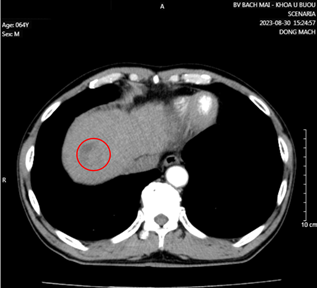

- Cắt lớp vi tính lồng ngực có tiêm thuốc cản quang:

Hình 1. Khối u kích thước 51x58x42mm thùy trên phổi trái, ngấm thuốc không đều sau tiêm (vòng tròn đỏ).